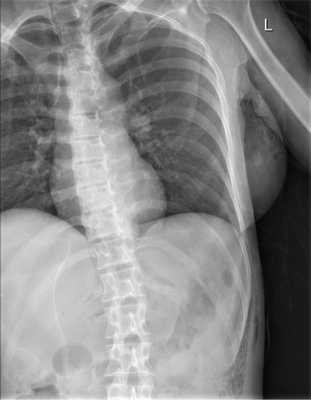

Больная М., 48 лет, поступила в приемное отделение НИИ СП им. Н.В. Склифосовского с жалобами на боль в левой половине живота, общую слабость, на 2-е сутки с момента получения травмы (удар копытом лошади в живот). При осмотре отмечены болезненность при пальпации грудной клетки слева, в левых отделах живота, развитие подкожной эмфиземы грудной клетки.

При рентгенологическом исследовании органов грудной клетки и брюшной полости (рис. 1) Рис. 1. Рентгенограмма органов грудной клетки и брюшной полости больной М. при поступлении. выявлена подкожная эмфизема слева от переднего отрезка VI ребра с переходом на брюшную полость. При УЗИ в 5 областях брюшной полости определяется свободная жидкость.

В экстренном порядке выполнена диагностическая видеолапароскопия. При ревизии в брюшной полости около 1000 мл мутного содержимого во всех отделах. Париетальная и висцеральная брюшина тусклая, с наложением фибрина, гиперемирована. При ревизии париетальной брюшины передней брюшной стенки в левом подреберье визуализирован дефект париетальной брюшины и разрыв внутренней косой, поперечной мышц без активного кровотечения размером 4×3 см. Принято решение о конверсии — выполнена широкая срединная лапаротомия. При ревизии тонкой кишки непосредственно за связкой Трейца обнаружен разрыв тощей кишки на 1/3 по противобрыжеечному краю (рис. 2), Рис. 2. Признаки перитонита и разрыва тонкой кишки (интраоперационные фотографии). при осмотре сальниковой сумки выявлено геморрагическое пропитывание парапанкреатической клетчатки. Выполнена назоинтестинальная интубация. Произведена мобилизация участка тощей кишки из-под связки Трейца с иссечением краев разрыва стенки тощей кишки, ушиванием разрыва тощей кишки в поперечном направлении двухрядным швом. Прядь большого сальника фиксирована к линии швов на тощей кишке. Выполнена санация брюшной полости 4 л 0,9% раствора NaCl. Ушит травматический разрыв мышц передней брюшной стенки, двухпросветный дренаж оставлен в ране, выведен через контрапертуру на переднюю брюшную стенку. Двухпросветные дренажи также установлены в подпеченочное пространство справа, в полость малого таза, в левый латеральный канал. С целью дренирования полости сальниковой сумки установлен однопросветный дренаж.